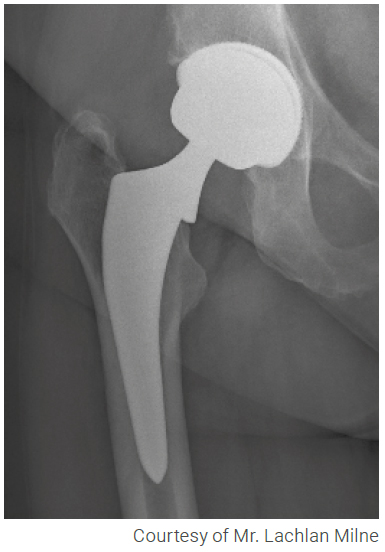

As part of the comprehensive Mpact System, Mpact 3D Metal Monocer is Medacta’s hemispherical cementless monoblock cup, featuring a 3D-printed shell with a built-in ceramic liner.

Mpact 3D Metal Monocer features a 3D-printed shell with a high-friction porous structure, providing effective treatment for demanding patients while promoting both primary stability and secondary fixation.

The Mpact 3D Metal Monocer cup features a 10 mm shell-to-head clearance, allowing it to be paired with large ceramic femoral heads. Larger diameter heads provide enhanced stability[1] by increasing the jumping distance and offering a greater range of motion compared to the articulation of conventional small diameter heads. This leads to improved functionality and stability[1], while also reducing the risk of dislocation.

Mpact 3D Metal Monocer combines advanced materials and manufacturing technologies. The 3D Metal Monocer shell features an advanced biomaterial structure that is finely engineered for the bone. It is made from a titanium alloy (Ti6Al4V) and produced using 3D printing technology.

3D Metal enables the design and manufacture of implants with a high coefficient of friction (μ), enhancing grip at the bone interface and providing superior primary stability[3,4]. Additionally, key parameters of the 3D Metal’s porous structure, such as pore size and porosity, can be precisely designed and controlled. These factors are essential for achieving an efficient biological fixation[5]. The efficient connection with the bone has been validated through an animal study[4].